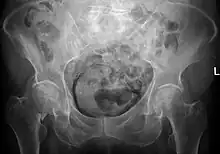

| Emphysematous cystitis as incidental finding in a case of hip fracture on the right | |

Due to the atypical presentation and rarity of the infection, it takes a physician longer to diagnose than more common types of bladder infections. Diagnosis requires a personalized investigation with consideration to risk factors and symptoms.[6] Radiology of the abdominal or pubic region has proven to be an important tool in reaching a definitive diagnosis of conditions causing gas in the urinary tract. Computer tomography, or CT scans, are of most help due to their high sensitivity in detecting gas and air bubbles.[10] However, radiology is normally not the first tool used to diagnose. Most diagnoses are made by chance after imaging examination.[7] Sometimes, even when patients don't show symptoms, their Emphysematous cystitis infection level can be very advanced already.[5] Gas in the bladder wall will often have the appearance of cobblestone or a “beaded necklace” with the use of conventional radiography.[7] Delayed diagnosis can lead to a severe infection, extension of the uterus, rupturing of the bladder, and death. Emphysematous cystitis has an overall mortality rate of 7%. However, surgery is only considered in severe cases where the disease progresses involving the ureters, kidneys, or adrenal glands. When required, surgery may be extensive.[5]